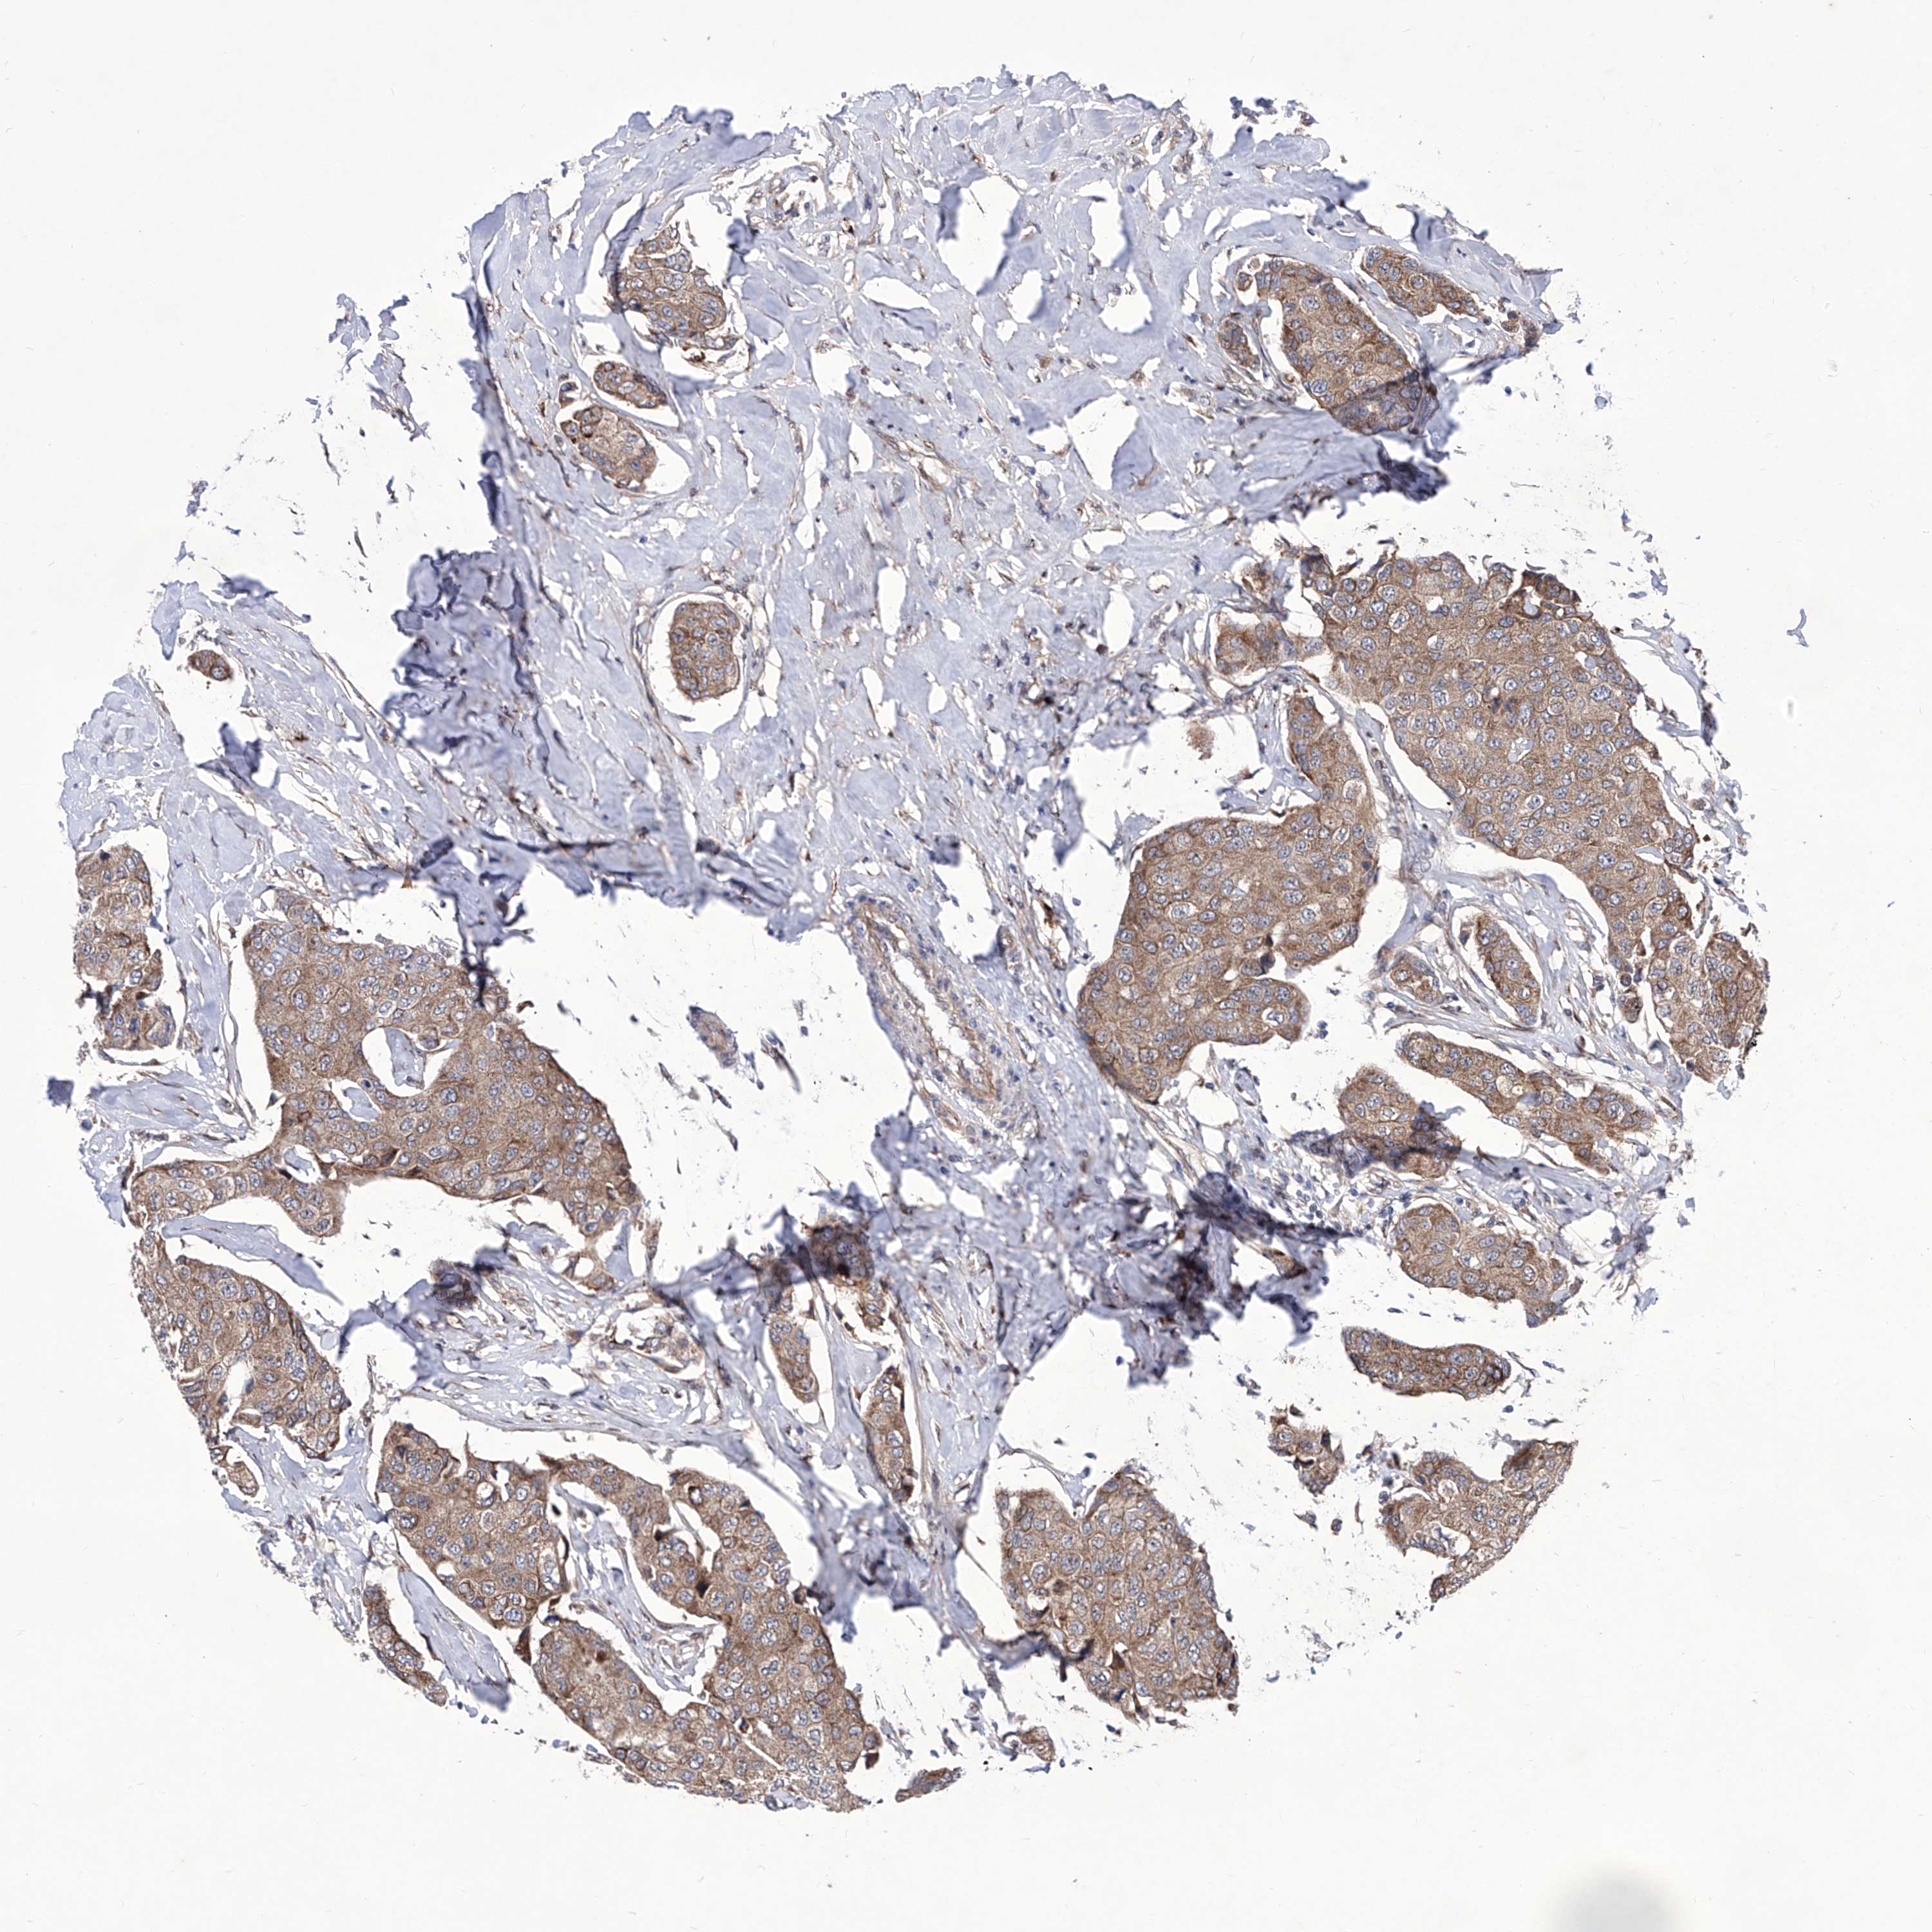

CANCER BREAST CANCER Show tissue menu

BRCA TCGA BRCA VALIDATION PROTEIN EXPRESSION